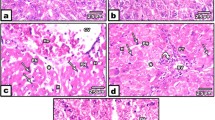

Dimethoate is a widely used organophosphate insecticide known to be toxic to the pancreas. The aim of this study is to detect the possible protective effects of the fenugreek seed ethanolic extract on the biochemical, histological, and ultra-structural abnormalities induced by dimethoate chronic exposure in the pancreas of adult male rats. The study was conducted on 50 adult male albino rats that were divided equally into 5 groups: (group I) negative control, (group II) vehicle control group, (group III) fenugreek-treated group that was given 400 mg/kg ethanolic fenugreek seed extract once daily, (group IV) dimethoate group received 20 mg/kg/day dimethoate, and (group V) dimethoate- + fenugreek-treated group received a combination of dimethoate and fenugreek in the same previous doses. Dimethoate treatment caused a significant increase in serum glucose, amylase, and lipase levels and a significant decrease in serum insulin. A significant increase in lipid peroxidation and pro-fibrotic cytokine (TGF-β1) together with a significant reduction of the antioxidant {reduced glutathione (GSH), catalase (CAT), superoxide dismutase (SOD)} activities and the anti-inflammatory (IL-4) in pancreatic tissues was also recorded. There was a histological and ultra-structural evidence of pancreatic acinar and islet cell injury. The recorded abnormalities were reversed in dimethoate+fenugreek treated group indicating that fenugreek ethanolic extract can serve as an antidote for dimethoate-induced pancreatic insult.

Hagar HH, Fahmy AH (2002) A biochemical, histochemical, and ultra-structural evaluation of the effect of dimethoate intoxication on rat pancreas. Toxicol Lett 133:161–170

Kamath V, Rajini PS (2007) Altered glucose homeostasis and oxidative impairment in pancreas of rats subjected to dimethoate intoxication. Toxicology 231(2–3):137–146. https://doi.org/10.1016/j.tox.2006.11.072

Kamath V, Joshi AKR, Rajini PS (2008) Dimethoate induced biochemical perturbation in rat pancreas and its attenuation by cashew nut skin extract. J Nutr Biochem 90:58–65